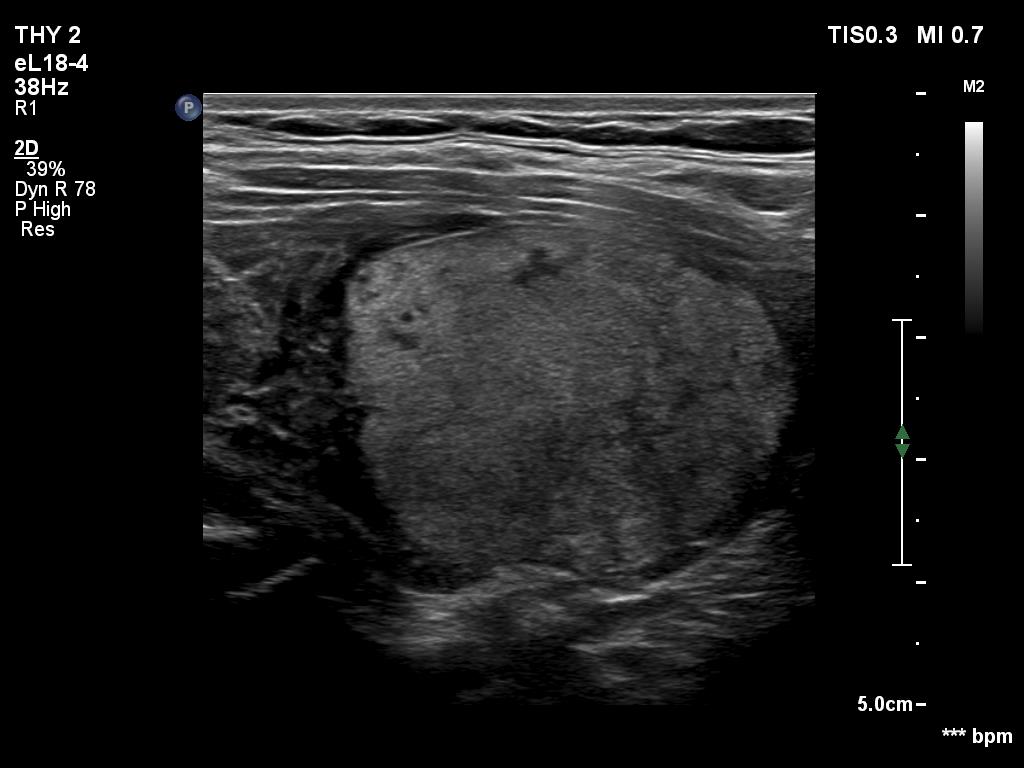

Benign nodule in Hashimoto's thyroiditis (cytology) - case 1286

Longitudinal scan

The iso/hyperechoic nodule has irregular margins. However, these are caused not by the infiltrative growth of the nodule but the infiltrative nature of the underlying autoimmune thyroiditis. Therefore, this nodule is an EU-TIRADS 3 lesion.